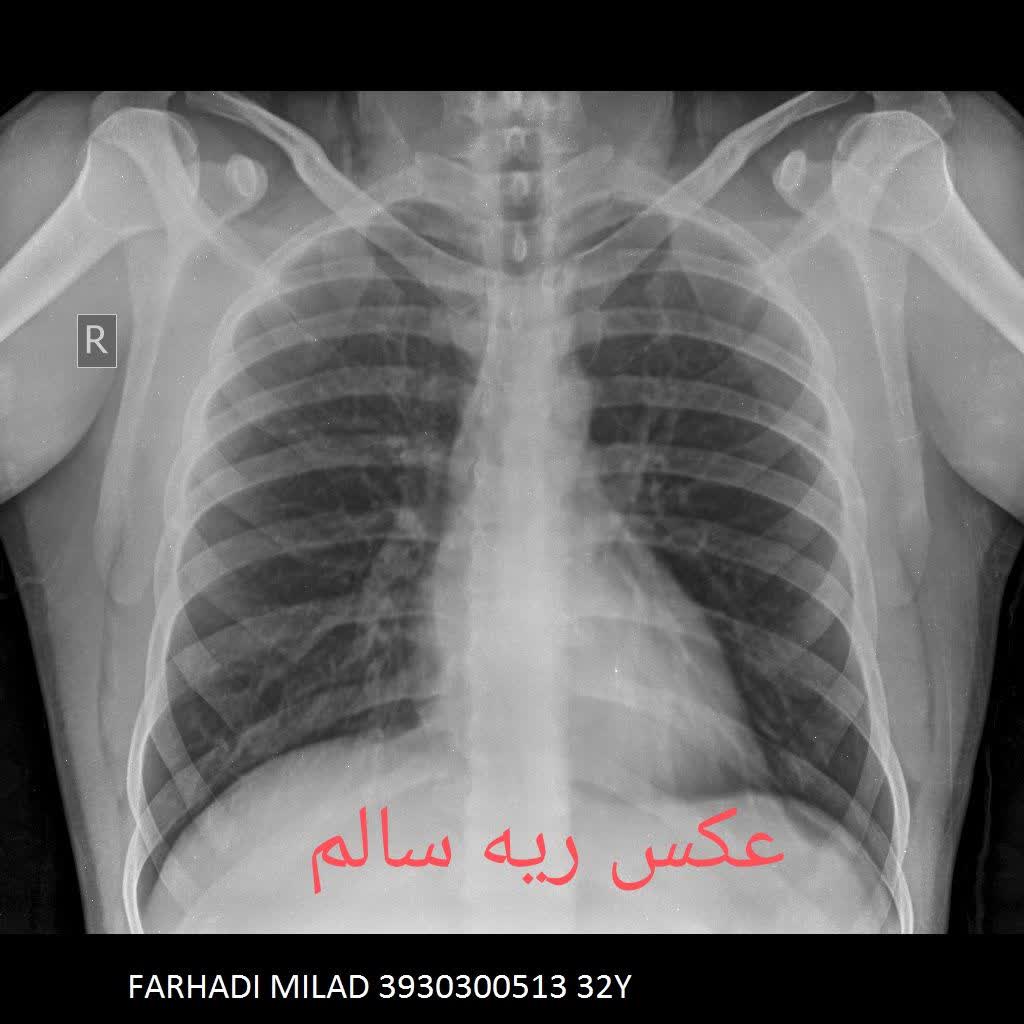

مقایسه عکس ریه سالم و ناسالم

در عکس ریه سالم و ناسالم، تفاوتها معمولاً با چشم غیرمسلح نیز مشهودند. ریه سالم تصویری یکنواخت و شفاف دارد، با خطوط ریوی طبیعی و بدون سایه یا توده. در مقابل، ریه ناسالم ممکن است سایههای غیرطبیعی، نواحی سفید شده (indicative of consolidation)، خطوط پررنگتر ناشی از فیبروز یا تودههای نامنظم را نمایش دهد. تشخیص این تفاوتها توسط پزشک رادیولوژیست، نیاز به تجربه و تجهیزات باکیفیت دارد، چیزی که در خدمات رادیولوژی ریه در منزل تهران و رادیولوژی ریه در منزل کرج فراهم شده است.